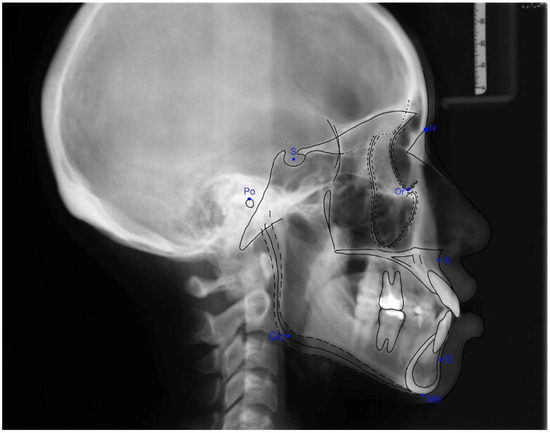

2.5. Assessment of Facial Pattern

The Frankfort–mandibular plane angle (FMA) and sella-nasion to mandibular plane (SN–MP) angle were applied to define three facial patterns in orthodontics (Figure 4 and Figure 5). The average angle of FMA was between 27 degrees and 34 degrees, and FMA smaller than 27 degrees was defined as low angle patient, and FMA larger than 34 degrees was defined as high angle patient.

Figure 4. Frankfort–mandibular plane angle (FMA). The FMA was constructed by the intersection of the Frankfort horizontal plane and the mandibular plane.

Figure 5. Sella-nasion plane to the mandibular plane (SN–MP) angle. The SN-MP angle was formed by the intersection of the SN plane and the mandibular plane.